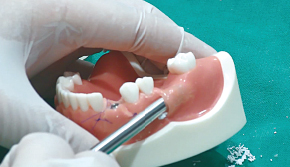

2. Bone Carrier로 골이식재 수집

3. Bone Carrier로 골이식재 수집